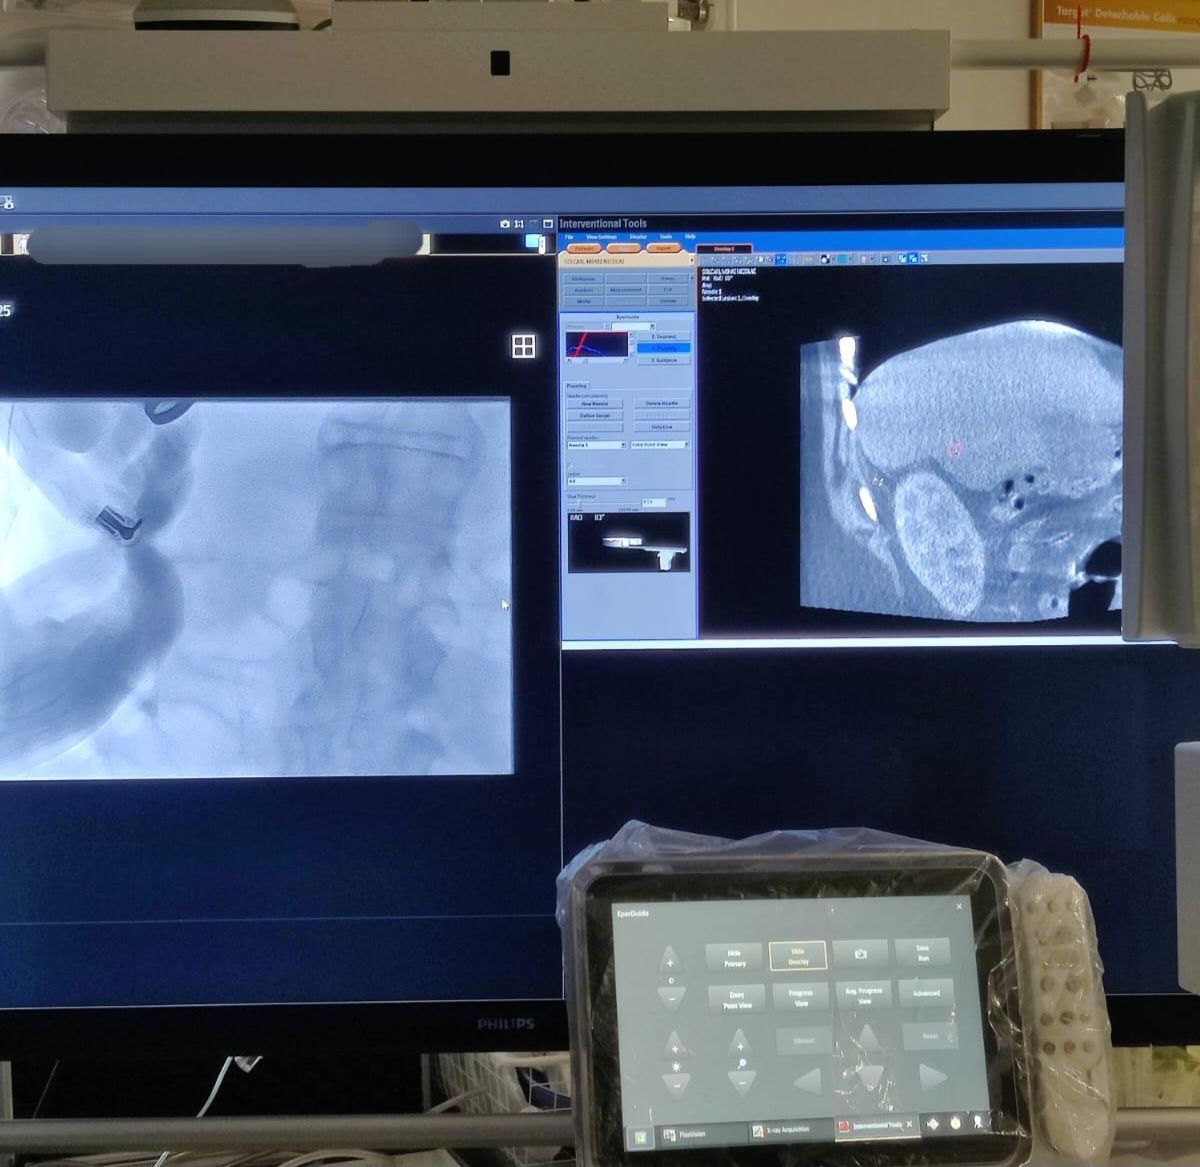

Spitalul Universitar de Urgență București (SUUB) a realizat a zecea procedură de ablație cu microunde pentru tumori hepatice, marcând totodată prima intervenție din România efectuată sub ghidaj Cone-Beam CT.

Prima ablație hepatică ghidată prin Cone-Beam CT a fost efectuată pentru un pacient în vârstă de 50 de ani. Până în prezent, zece pacienți cu vârste între 50 și 86 de ani au beneficiat de tratament minim invaziv pentru tumori hepatice primare sau metastaze, utilizând diferite tipuri de ghidaj imagistic disponibile la SUUB: ecografic, CT și, cel mai recent, Cone-Beam CT.

Cone-Beam CT este o tehnologie imagistică avansată, care permite obținerea de imagini tridimensionale în timp real, direct în sala de proceduri. Comparativ cu ghidajul CT clasic, CBCT oferă:

Vizualizare 3D instantanee a tumorii și a țesuturilor înconjurătoare

Precizie maximă în plasarea acului de ablație

Reducerea timpului de procedură și a expunerii la radiații

Posibilitatea de a ajusta tehnica în timp real